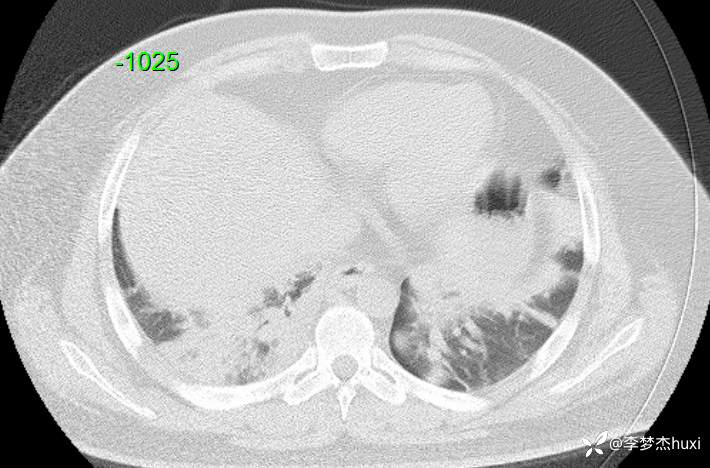

【现病史及既往史】: 1.患者青年 男,患者缘于2天前无诱因出现胸痛,为前胸痛,伴后背疼痛,咳嗽及深呼吸时明显,伴咳嗽,痰不易咳出,伴恶心、呕吐,伴发热,体温最高达37.7℃,无寒战,无咯血,院外未应用药物治疗,症状无明显好转,为求进一步治疗来院就诊,门诊查胸部CT提示:双肺炎症,较前进展,双肺纹理增重,右肺实性结节,建议随诊复查,双侧胸膜局部增厚,右侧胸腔少量积液。以“肺炎”收住院;。

【检查】: 4.辅助检查:心电图示:窦性心动过速,门诊查胸部CT提示:双肺炎症,较前进展,双肺纹理增重,右肺实性结节,建议随诊复查,双侧胸膜局部增厚,右侧胸腔少量积液。